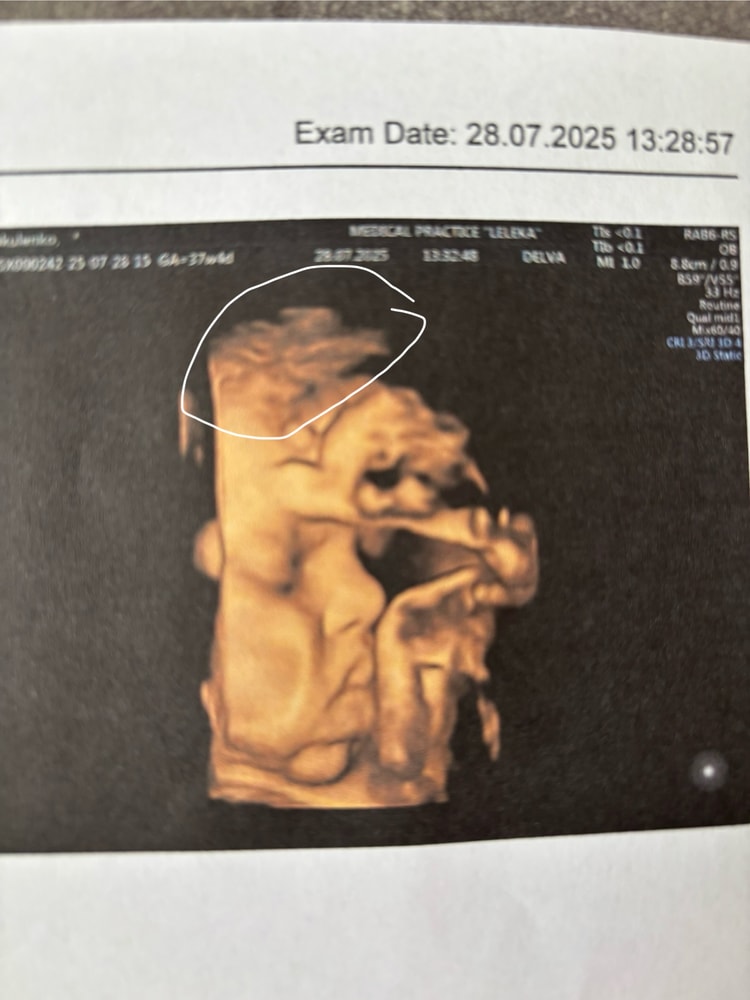

Всё о родах (ЕР, КС, вопросы о родоразрешении)Малышка готова к рождению, по узи вес 3400, полностью дозревшая мадам, с волосиками(обвела на снимке) и пухлыми губками, как я себе и представляла😍

Назначили 06.08 дату ПКС. Ровно неделька до встречи!!!! Ухххх сколько волнения!!!!